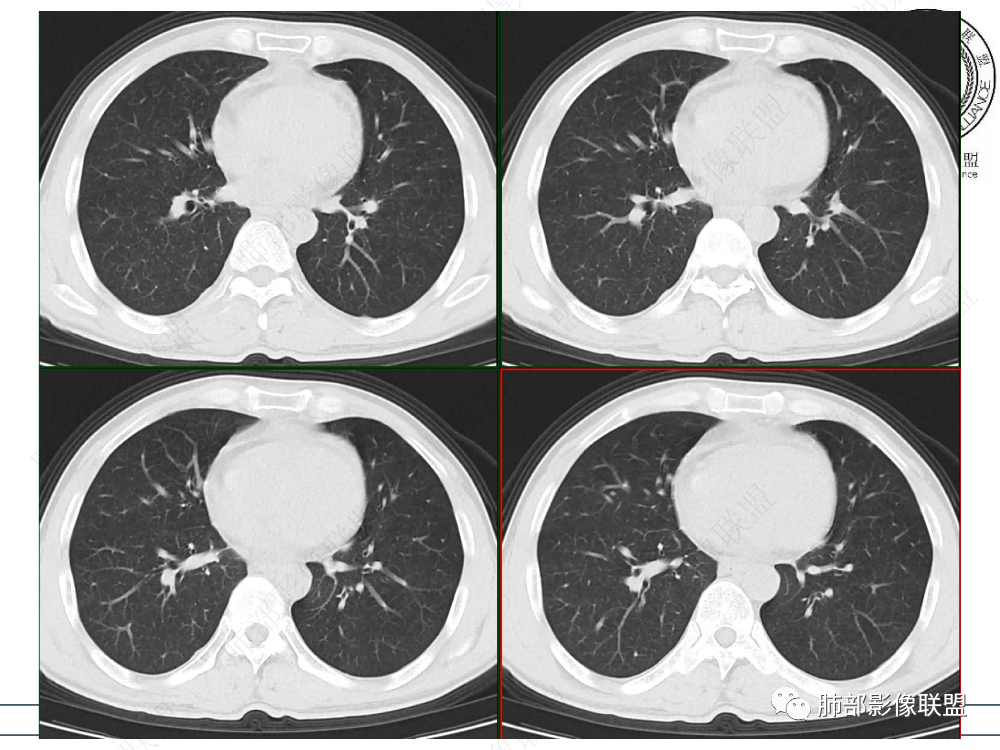

1.临床资料:中老年男性,病史较长-8个月,主诉胸痛,实验室资料:乳酸脱氢酶(LDH)升高。

2.影像表现:前上纵隔较大肿块,密度不均,形态不规则,边界不清,有结节样突起,脂肪间隙显示不清。病灶侵犯左无名静脉及上腔静脉,其中左无名静脉闭塞(胸背部侧支循环明显,亦表明回流受阻)。增强后轻中度不均强化。坏死边界欠清晰。可见心包积液,提示心包受侵犯。右侧上叶及纵隔胸膜下结节影,疑胸膜肺转移可能。胸骨柄后缘皮质不完整,疑骨质破坏(未提供骨窗及矢状位图像)。左锁骨上可见肿大淋巴结。